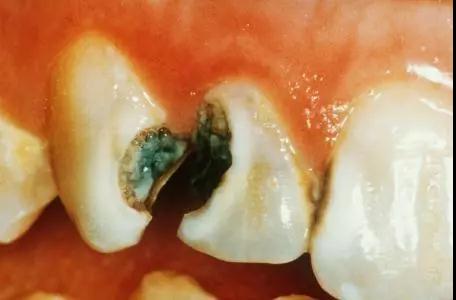

龋病

牙周病